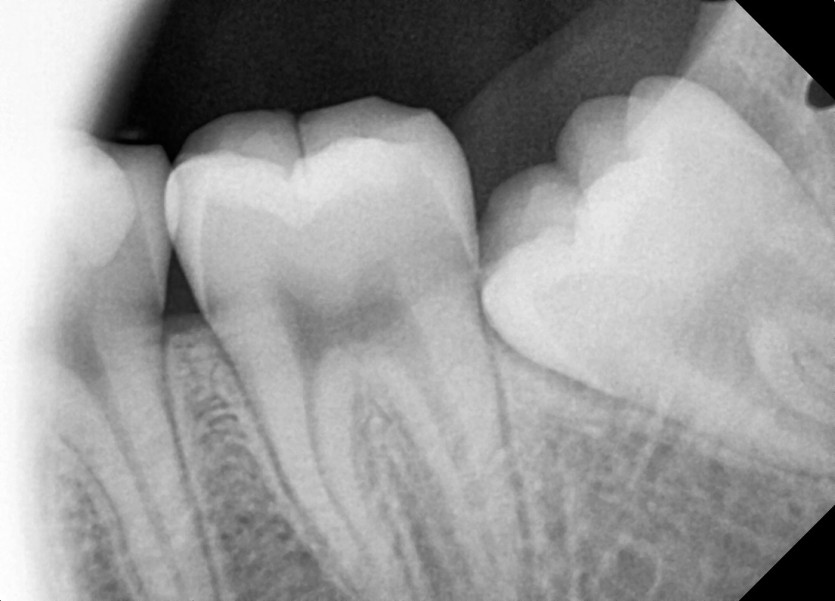

#28,29(과잉치),38 사랑니 발치

구강 외과 전문의가 당일 발치했습니다.